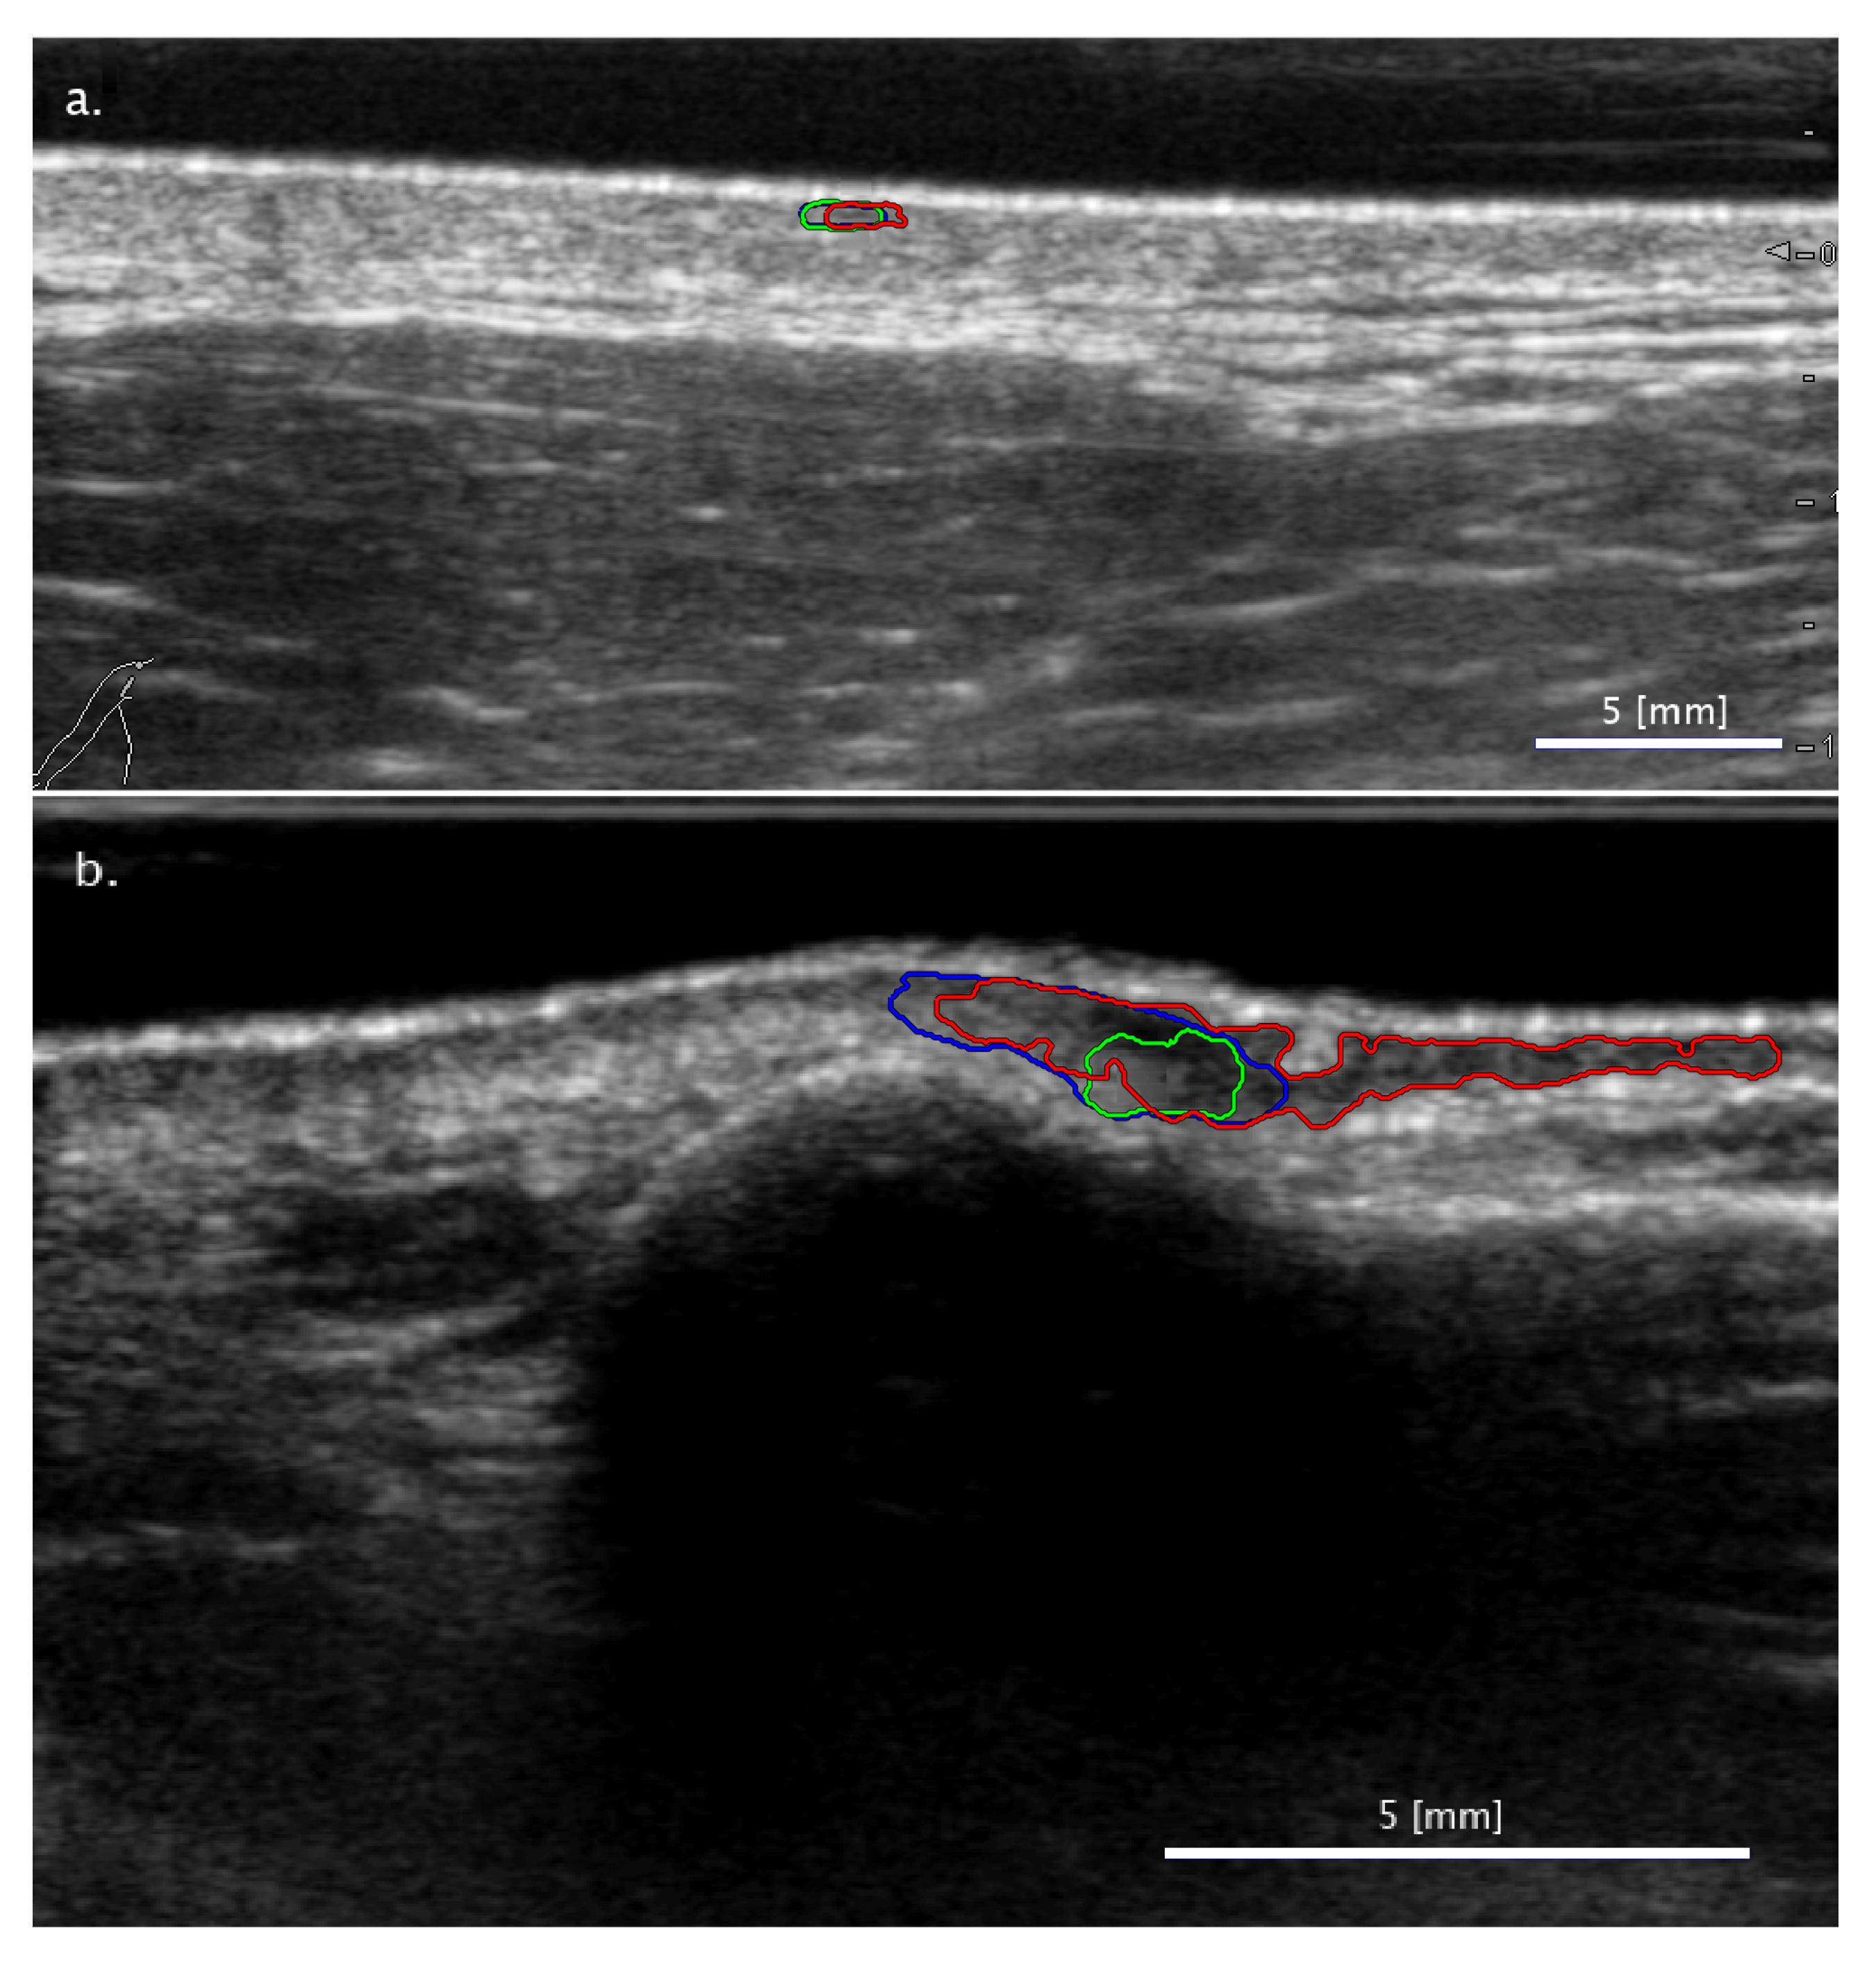

3.2. Comparison of FA and SA Classification Performance with Representative Images

3.2.1. Cases When FA Fails While SA Methods Perform Correctly

3.2.2. Cases When the Two SA Methods Return Different Classifications

3.2.3. Cases When the SA Methods Both Fail While the FA Method Performs Correctly

3.3. Sensitivity of Classification to Changes in Lesion Segmentation